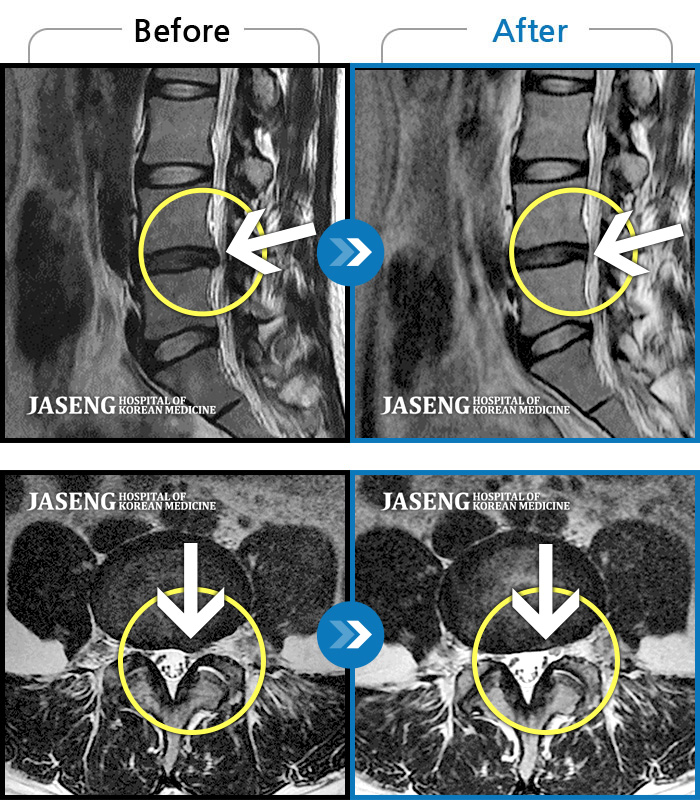

Before

After

환자에게 사전 동의를 받아 동일 조건에서 촬영되었습니다.

개인에 따라 치료 후 부작용이 발생할 수 있으니 의료진과 상담 후 치료를 진행하시기 바랍니다.

처음 내원 시 좌측 엉덩이가 많이 아프고, 좌측 다리로 저림이 심하며 특히 좌위시 하지 방사통이 심하여 1분도 좌위가 어려워 식사도 서서 하는 등 정상적인 활동이 힘든 상태였습니다.